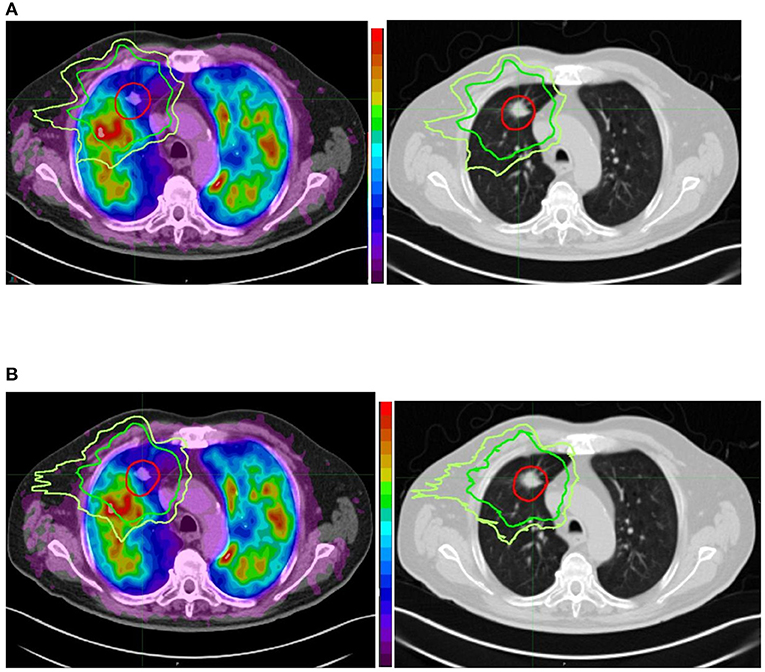

Kanker paru adalah salah satu penyakit yang paling sering mematikan di seluruh dunia. Deteksi dini sangat penting untuk meningkatkan peluang kesembuhan pasien. Citra Thorax CT scan adalah metode pencitraan medis yang kuat dalam mendeteksi kanker paru pada tahap awal, sehingga memungkinkan intervensi lebih dini dan pengobatan yang lebih berhasil.

Setelah segmentasi, langkah selanjutnya adalah deteksi lesi atau area yang mencurigakan dalam citra paru-paru. Ini dapat dilakukan dengan menggunakan teknik deteksi tepi, analisis tekstur, dan metode pembelajaran mesin.

Selanjutnya, fitur-fitur yang relevan diekstrak dari area yang mencurigakan. Fitur ini dapat mencakup ukuran, bentuk, tekstur, dan karakteristik lain yang dapat membantu mengidentifikasi apakah lesi tersebut kemungkinan kanker atau bukan.

Contoh penerapan pengolahan citra untuk deteksi kanker paru berdasarkan citra thorax CT Scan ditunjukkan pada video berikut ini: